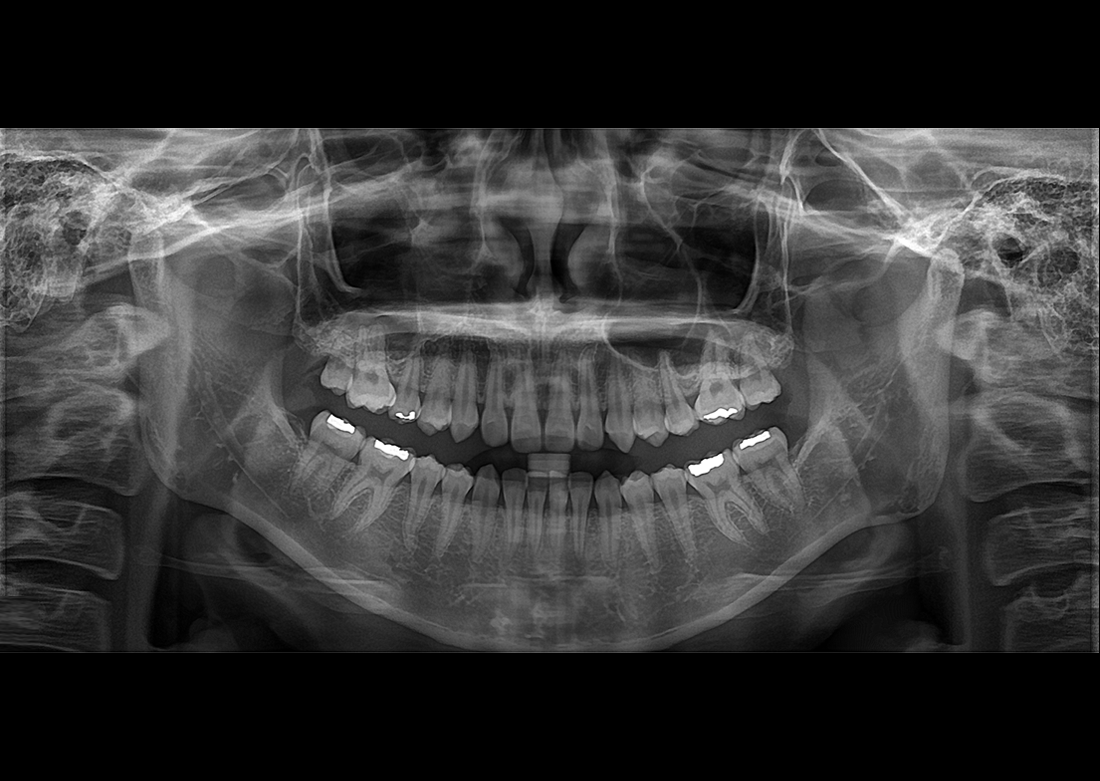

KLİNIKAI KÉPEK

Kiváló diagnosztikai képalkotás több éves tapasztalattal és szakértelemmel.

A Genoray büszkesége, amelyet világszerte elismernek és szeretnek.